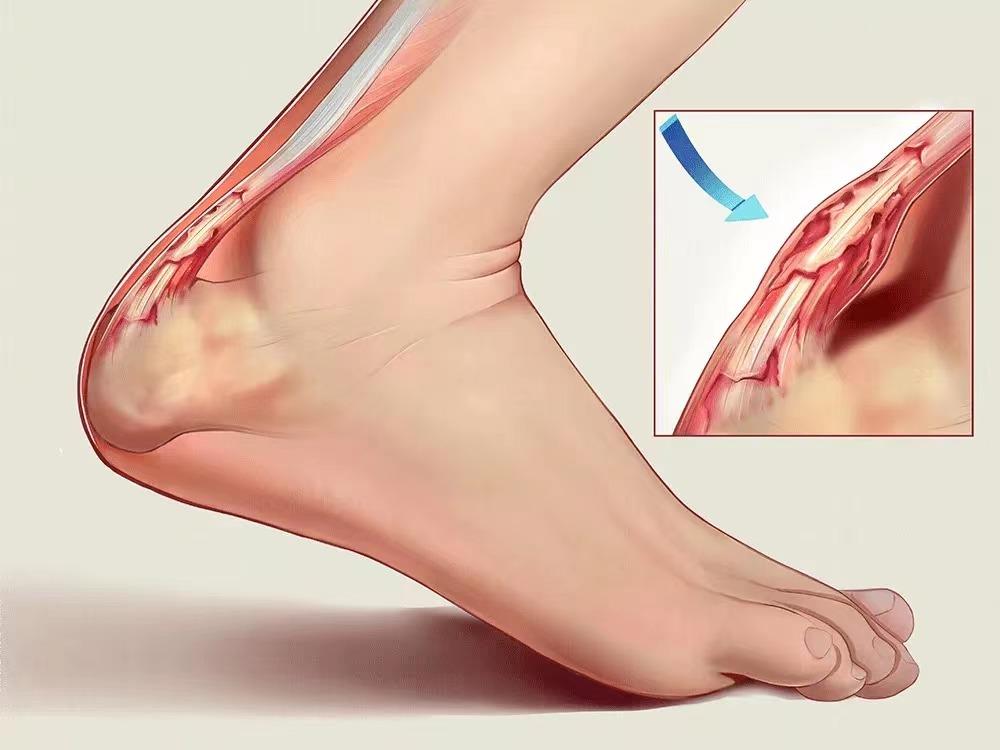

(二)跟腱炎

小腿远端后方或脚后跟的轻微疼痛,也可能表现为剧痛,如果忽视的话,会变得更剧烈。

跟腱是人体最粗的肌腱,连接腓肠肌(小腿肌肉)和跟骨(足跟),它是足蹬地的主要动力来源。跟腱炎是一种常见的过度使用损伤,当你在训练中增加强度(以更快的速度跑步或大幅度增加里程),在跟腱止点部位会出现反复微损伤,最终导致跟腱的变性。

治疗/预防 :由于跟腱在运动中起着非常重要的作用,当它出现炎症时,常需要一段时间来愈合。当你的脚后跟上方出现疼痛,就意味着是时候要休息了,一般休息4到6周的时间就会感觉好些。而如果在疼痛的状况下继续跑步,则会引发更多麻烦,严重的会引起跟腱断裂。因此,一旦你已经有跟腱止点的疼痛,停止跑步,而不是继续运动让它变得更糟再进行康复。